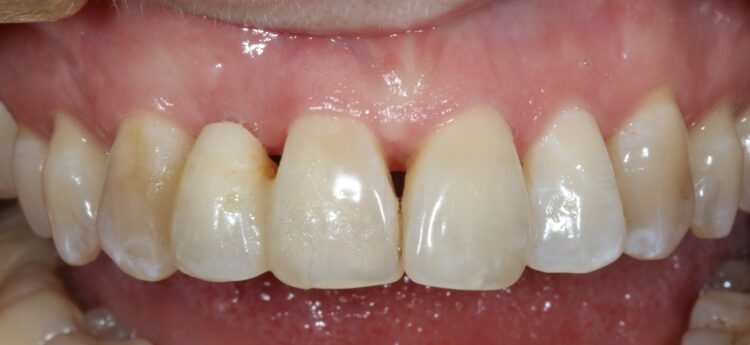

A female patient was referred for implant replacement of her failed upper right lateral incisor tooth. The tooth exhibited grade III mobility and had drifted forwards and downwards.

Clinical and CT scan assessment confirmed that the UR2 suffered from extensive bone loss with complete loss of the labial plate and was associated with a large periapical lesion which extended palatally and laterally towards the UR3. The UR3 tested positive to vitality testing.